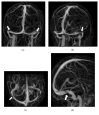

Results: Seventy-nine patients were diagnosed with IIH. Bilateral transverse sinus stenosis (TSS) was found in 74% of the population. Visual outcome at 6 months was poor for 46% of patients, including all patients presenting weight gain of at least 5% since diagnosis (p < 0.001), whereas mean body mass index at diagnosis was not different between patients with poor versus good outcome (32.9 ± 7.7 versus 34.6 ± 9.4 kg·m-2). Other significant factors of poor prognosis were bilateral TSS (OR = 5.2; 95 CI: 1.24-24.9; p = 0.024). Thirteen patients with poor outcome after 6-month assessment underwent unilateral TSS stenting leading to visual improvement in 11 cases.

Conclusion: Weight gain, rather than initial weight, emerged as the leading factor of poor visual outcome in patients with IIH, followed by presence of bilateral TSS. Consequently, first-line treatment must include dietary measures to control weight. Unilateral stenting appears to be a safe second-line treatment option for patients with bilateral TSS.